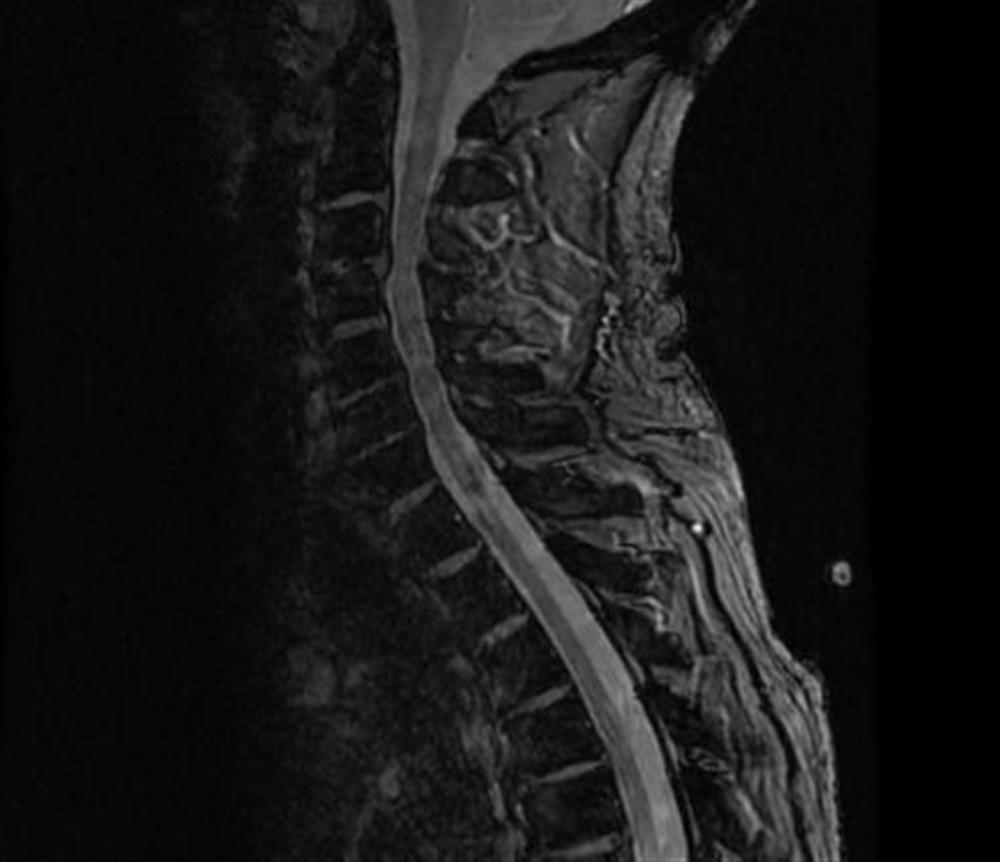

From www.orthobullets.com

Spinal Cord Injuries Spine Orthobullets Incomplete Spinal Cord Injury Physical Therapy Defined as spinal cord injury with some preserved motor or sensory function below the injury level including: Recent pieces of evidence about the efficacy of gait rehabilitation for incomplete spinal cord injury remain unclear. Walking dysfunction is common in individuals with an incomplete spinal cord injury, arising not only from the impairments associated with the spinal. This affects the conduction. Incomplete Spinal Cord Injury Physical Therapy.